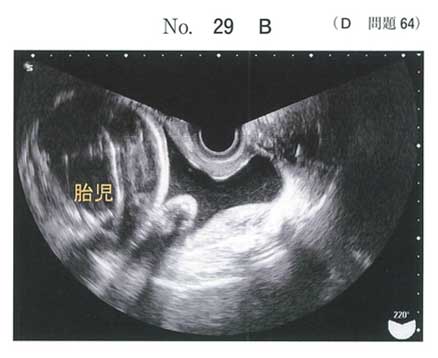

| タイトル:113D-64 | コメント数:5 | 割問 |

32週で成長も問題ないのでステロイドによる臓器成熟はいらないかと思いましたが、微妙ですね…

BDは論外、子宮収縮は来ているのでCは絶対やる

32週、、、微妙なところだけど子宮口は閉鎖しているからすぐに生まれそうな感じではない。少なくともあと2週間は持ちそう。